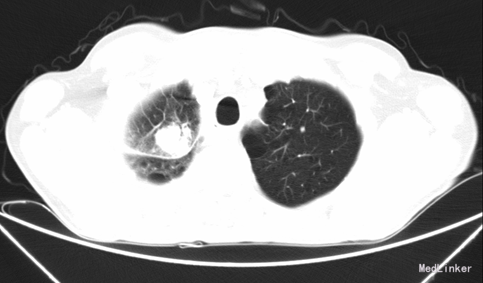

患者为中年男性。因“右肺癌术后2年,右胸疼痛2+月”入院。患者2年前于外院行“右肺癌根治术”,术后病检示:右上肺中-低分化腺癌,术后行4期NP方案化疗治疗。1-年前于乐山市人民医院复查CT示右肺中叶肺癌?行6周期TP方案化疗及放疗28次,复查胸部CT示右肺肿物较前增大。

PCT/CT示:右肺癌术后放化疗后:1、右肺中叶糖代谢增高肿块,最大截面约39*29mm,考虑肿瘤复发;右侧胸腔少量包裹性积液;右侧第6肋后段术后改变。

诊断:1、右肺中叶肿块:右肺上叶腺癌术后复发?2、右肺上叶腺癌(T3N0M0 II期)术后放化疗后 。在全麻下行:经右胸右肺中叶外侧段切除+淋巴结清扫术。